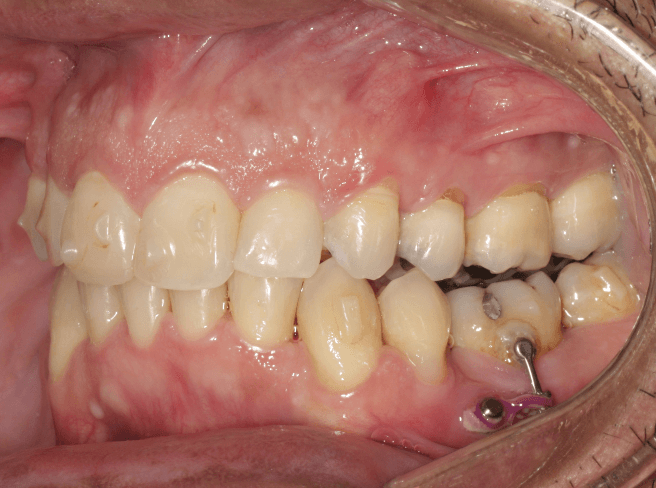

Doença Periodontal Ativa:

Pacientes com doenças gengivais avançadas podem não ser candidatos ideais para alinhadores, pois a movimentação dentária pode agravar a condição.

O tratamento ortodôntico em pacientes com doença periodontal deve ser realizado com muito critério e cuidado, sendo contraindicado o tratamento ortodôntico em pacientes com doença periodontal ativa.

Perda Óssea Significativa:

A perda óssea ao redor dos dentes pode comprometer a capacidade do alinhador de mover os dentes de forma eficaz e segura.

A movimentação ortodôntica pode exacerbar essa mobilidade, o que aumenta o risco de complicações como a perda do dente ou uma piora da condição da gengiva.